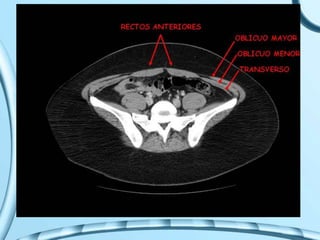

PLANOS DE LA PARED

ABDOMINAL

• Piel

• Fascias:

– superficial

• Fascia de Camper

• Fascia de Scarpa

– Profunda

• Músculos:

– Oblicuo mayor

– Oblicuo menor

– Transverso

• Fascia transversalis

• Grasa preperitoneal

• Peritoneo parietal

MUSCULOS

M. RECTO ANTERIOR